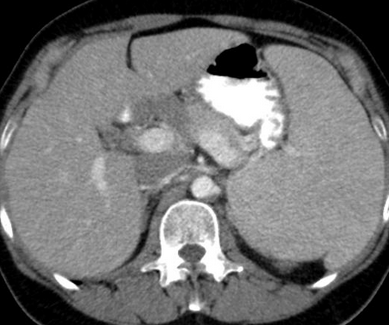

Polycystic liver disease. Red arrow. Infected hepatic cyst (Courtesy Dr. V. Penopoulos)